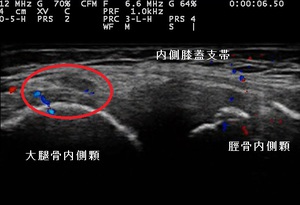

坂戸市小学生 肘の痛み 右肘内側上顆裂離骨折

右肘内側 超音波長軸像 左同部正常(健)側

坂戸市小学5年生男児、 少年野球クラブピッチャー。 肘の痛み、右肘内側上顆裂離骨折。

【原因】

2日前、野球の練習試合に4回まで投げたところで、右肘に痛みが走りピッチャーを交代しました。翌日の練習でも

痛みが引かず、当接骨院を受診されました。

右肘の内側上顆に圧痛、熱感、屈曲時痛、外転外旋(投球動作)時痛が著明でした。超音波観察において、

内側側副靭帯付着部(左右上画像黄色の囲み)の内側上顆前下部に、骨が裂離(剥離)している様子が

認められました(左上画像の丸内矢印)。肘外側には損傷はありませんでした。

小学生の内側野球肘は約4割に起こると言われ、特に小児の場合は成長期であるため、靭帯付着部が軟骨で

剥がれやすい特徴があります。成人になり骨の成長が終了すると、靭帯実質の損傷が多くなります。